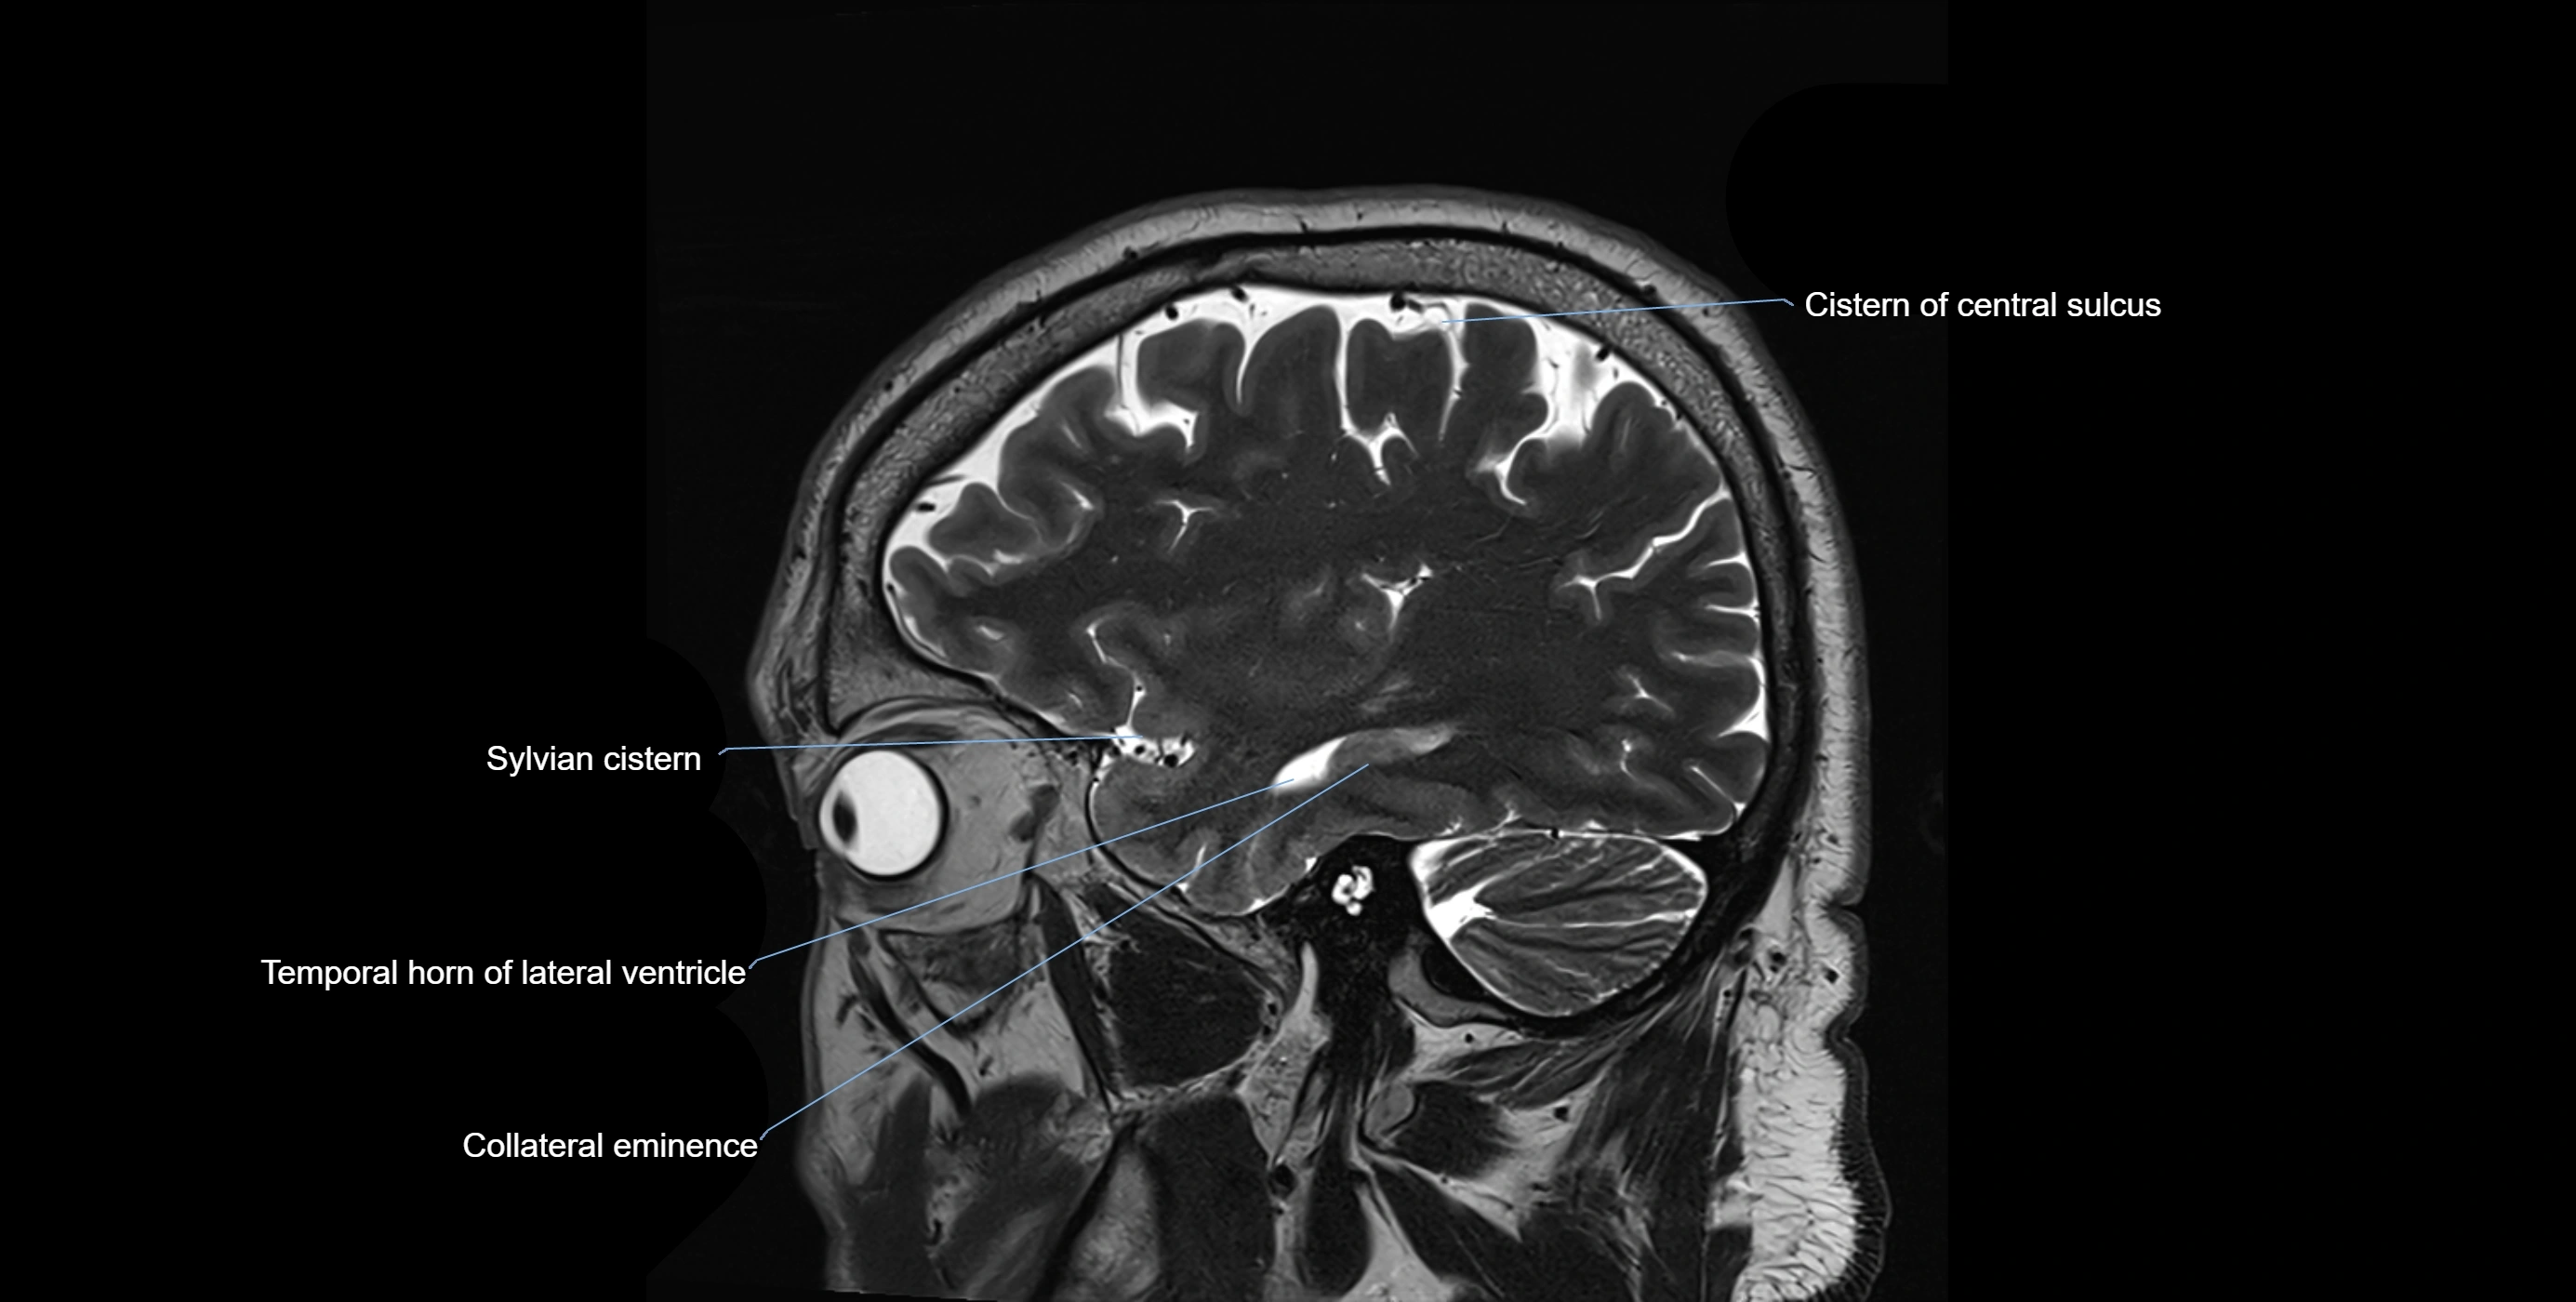

MRI images

image